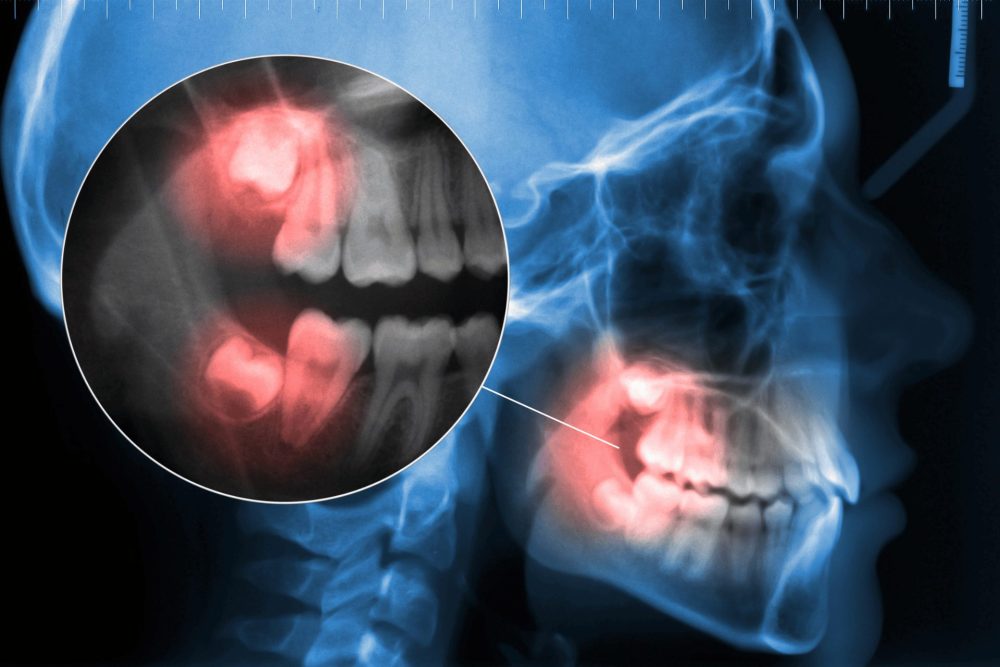

1.斜めや横向きに生えている

歯ぐきから顔を出しながら、斜めや横向きに生えている親知らずは、抜いた方がいいケースが多いです。

斜めに生えた親知らずは、隣の奥歯を圧迫し続けます。

長期間押されると、隣の歯の根っこが少しずつ溶けてしまう場合があります。

また、親知らずと隣の歯の間にできたすき間には、食べかすが溜まりやすく、歯ブラシの毛先も届きにくいため、汚れが残りがちです。

このままだと、親知らずだけではなく、隣の健康な歯まで虫歯になるケースも少なくありません。